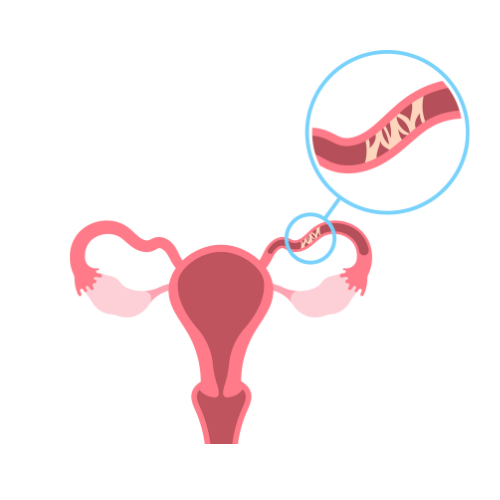

Tubal Ligation

Our gynecologist offers expert tubal ligation procedures, providing a safe and effective permanent contraception option to promote reproductive health and family planning.